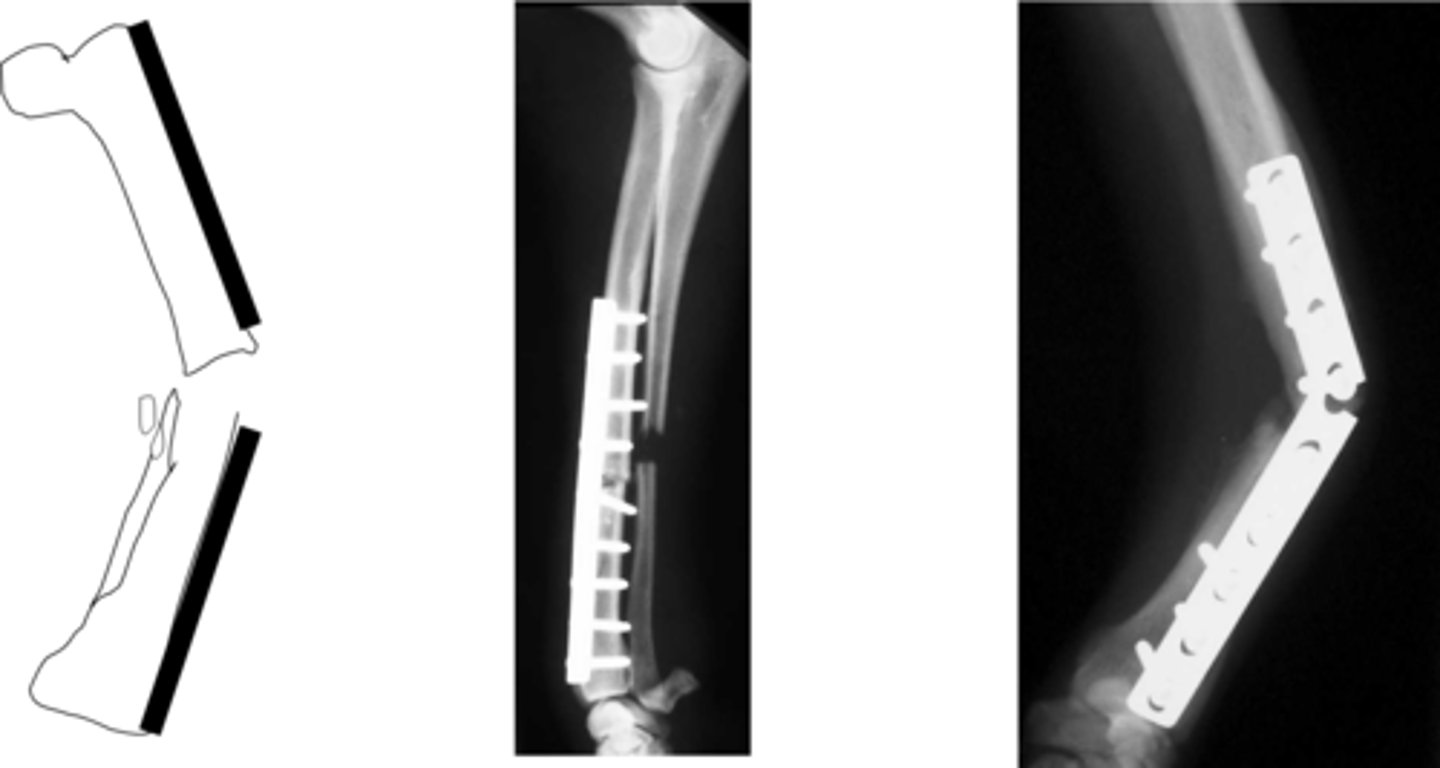

when to use plate fixation

-reconstruction of comminuted fractures

why use plate fixation

-protect against axial and rotational forces

buttress plate

-strong central section that bridges comminuted section of fracture

-plate takes all of load

cyclical loading leading to plate failure

-trans cortex and radius incomplete compounded by absence of section of ulna

-plate exposed to cyclical loading and failure, are prone to bending

-in humerus, femur and tibia can be managed with IM pin, rod plate combo